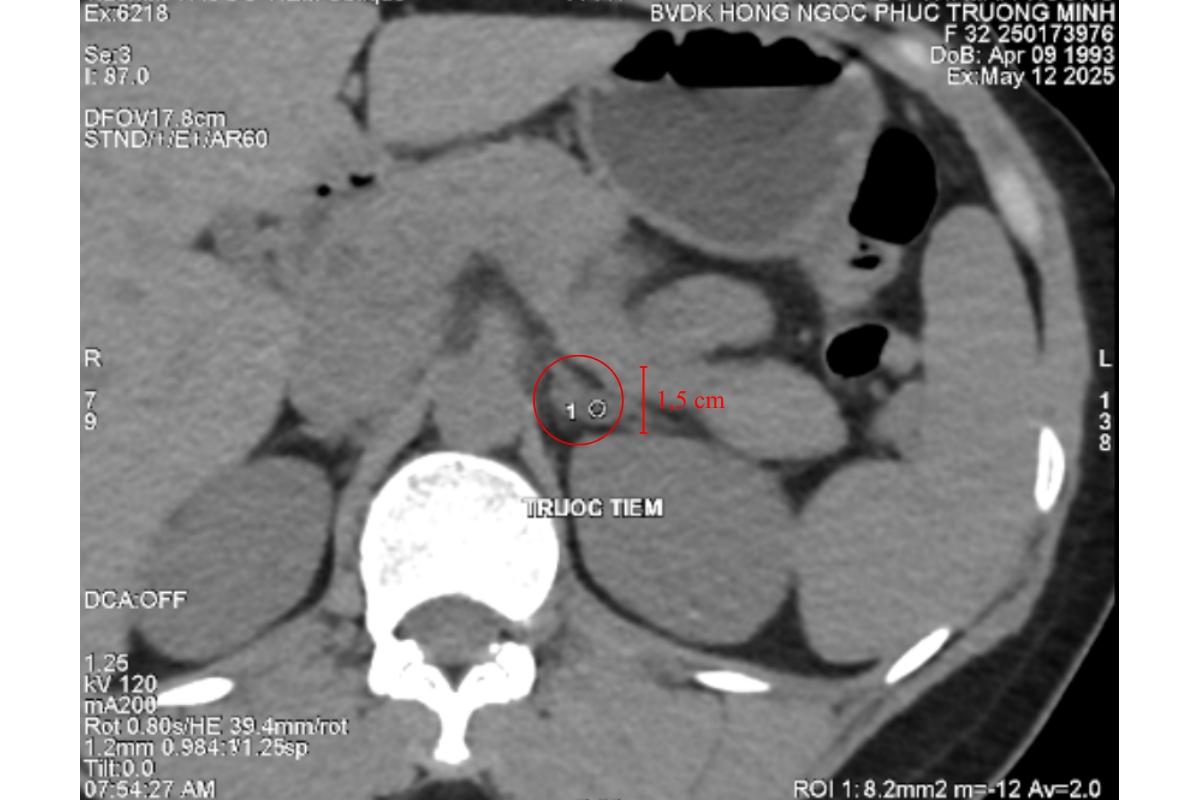

Trong một chuyến công tác tại Hà Nội, chị P quyết định đến thăm khám tại Bệnh Viện Đa Khoa Hồng Ngọc. Từ khai thác tiền sử và các triệu chứng lâm sàng, các bác sĩ nghi ngờ chị P mắc u tuyến thượng thận, một bệnh lý về nội tiết rất hiếm gặp, có thể thường xuyên gây tăng huyết áp đột ngột. Kết quả chụp cắt lớp vi tính ổ bụng không nằm ngoài dự đoán, chị P có 1 khối u tuyến thượng thận kích thước 1,5cm nằm ở tuyến thượng thận trái. ThS.BS CKII Trịnh Minh Thanh người trực tiếp thăm khám cho bệnh nhân nhận định: “Đây chính là nguyên nhân khiến bệnh nhân thường xuyên bị tăng huyết áp nội sinh, kéo dài suốt một thời gian nhưng chưa được phát hiện”.

Khối u tuyến thượng thận trái, kích thước 1,5cm

Dù kích thước chỉ 1,5cm khối u tuyến thượng thận nằm sâu trong khoang sau phúc mạc, gần đuôi tụy vị trí hẹp và gần nhiều cấu trúc quan trọng như mạch máu lớn và thận. Phẫu thuật nội soi trong trường hợp này đòi hỏi bác sĩ phải xác định chính xác vị trí khối u, kiểm soát tốt vùng mổ và thao tác khéo léo để tránh tổn thương mô lành. Với sự hỗ trợ của hệ thống nội soi hiện đại, sau 2 giờ ca mổ diễn ra an toàn, ít xâm lấn và hỗ trợ bệnh nhân hồi phục nhanh chóng.